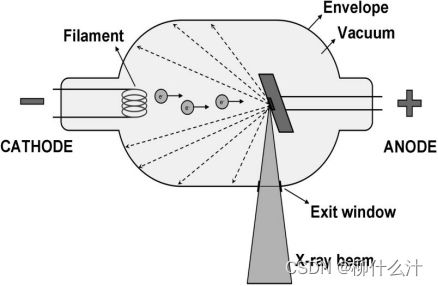

硬件方面,仅作了解:电流加热阴极的灯丝,通过热离子效应导致电子的释放,这些电子因为电位差被加速到阳极,通过电子和阳极的碰撞,产生x射线